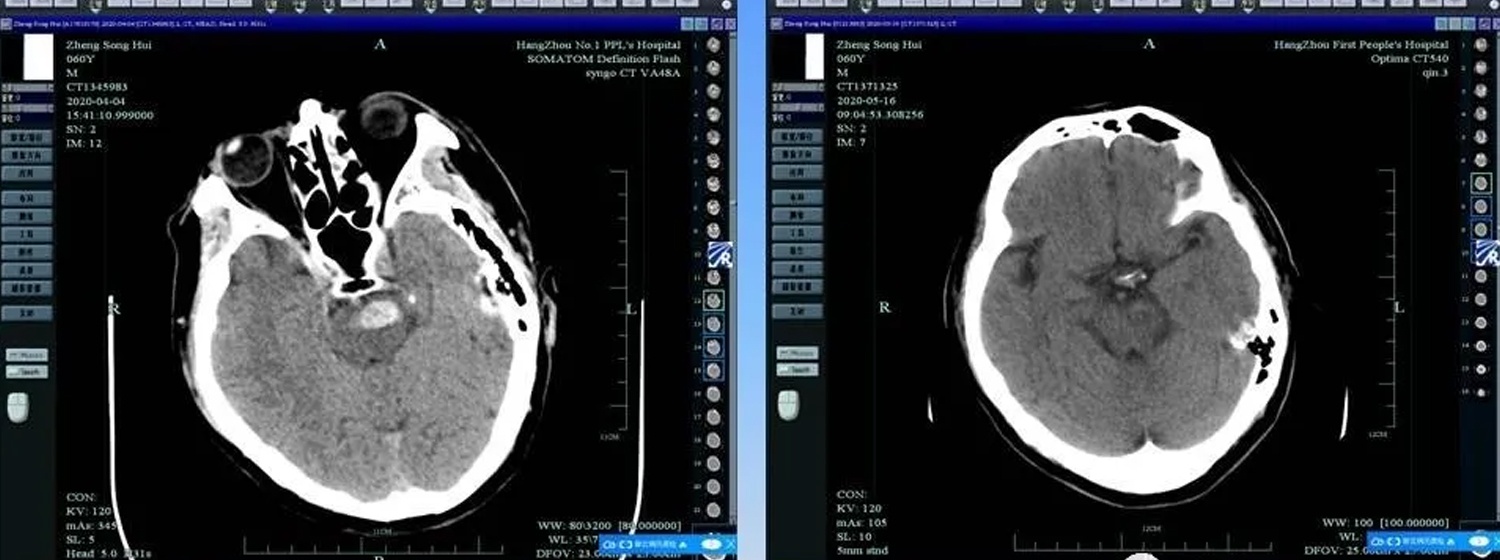

脑梗塞是指脑部血液供应障碍,缺血、缺氧、引起脑组织坏死软化而言……

脑梗死又称缺血性卒中,中医称之为卒中或中风。本病系由各种原因所致的……